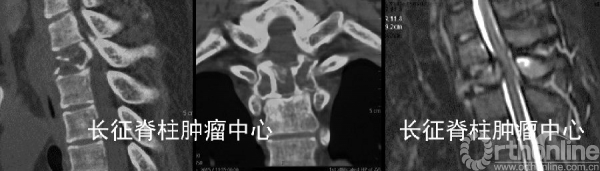

第一次术前CT、MRI均提示胸2椎体溶骨性破坏,。